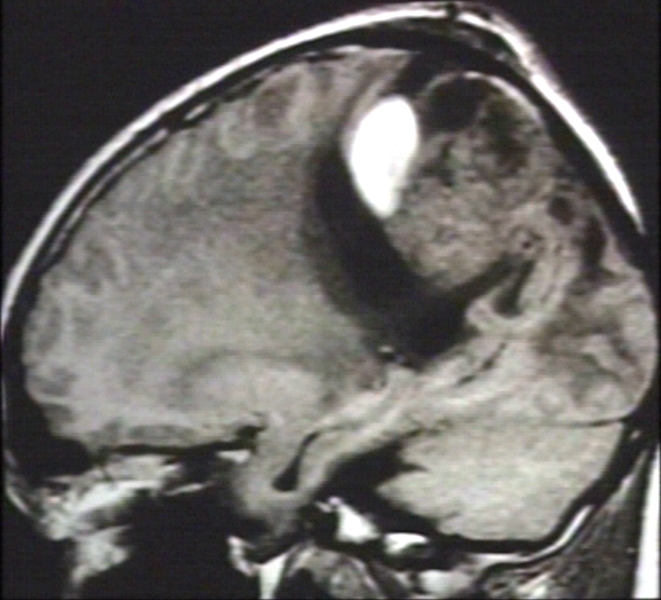

RADIOLOGY: NERVOUS: BRAIN: GLIOBLASTOMA WITH HEMORRHAGE; T1 (MRI)